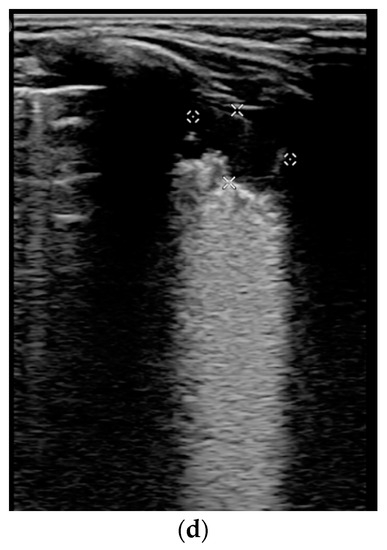

3.3. Lung ultrasound investigation, score and correlation

| Patients with respiratory involvement (n = 12) vs. patients without (n = 7)—Figure 5a | 6 vs. 3 [3; 7.5] vs. [2;3.75] | 12.12 vs. 6.37 | 16.50 | 0.02 |